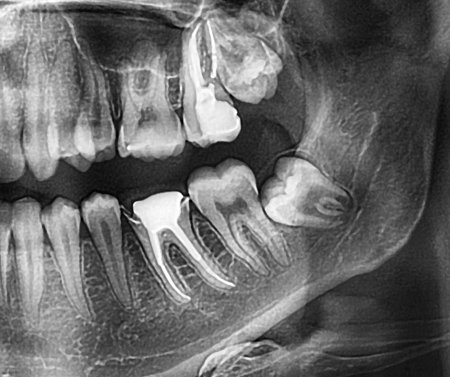

Dijagnoza se postavlja kliničkim pregledom i radiološkom analizom. Stomatolog najprije procjenjuje stanje desni, položaj umnjaka i opseg upale. Zatim se obično radi ortopan (rendgenska snimka cijele čeljusti) ili CBCT snimka, koja pokazuje točan položaj zuba i njegov odnos prema okolnim strukturama, poput živca donje čeljusti. U Smile Studiju Rijeka koristi se digitalna dijagnostika visoke rezolucije, što omogućuje precizno planiranje terapije i izbjegavanje komplikacija.

Upala umnjaka obično prolazi kroz nekoliko faza:

Početna iritacija desni – blaga bol i crvenilo, obično bez otekline.

Akutna upala – jaka bol, oteklina, ponekad otežano otvaranje usta.

Širenje infekcije – upala se može proširiti na okolna tkiva, obraze ili vrat.

Kronični perikoronitis – povremene epizode upale s lošim zadahom i mogućim gnojnim iscjetkom. U težim fazama nužna je hitna intervencija stomatologa, jer se infekcija može proširiti i na dublje slojeve tkiva.